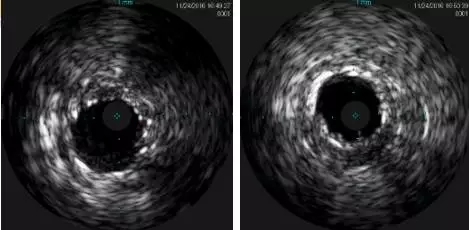

LAD-IVUS

LAD中段既往支架膨胀不良

导丝主要位于真腔

LCX-IVUS

LCX远端真腔,近端内膜下

IVUS结果